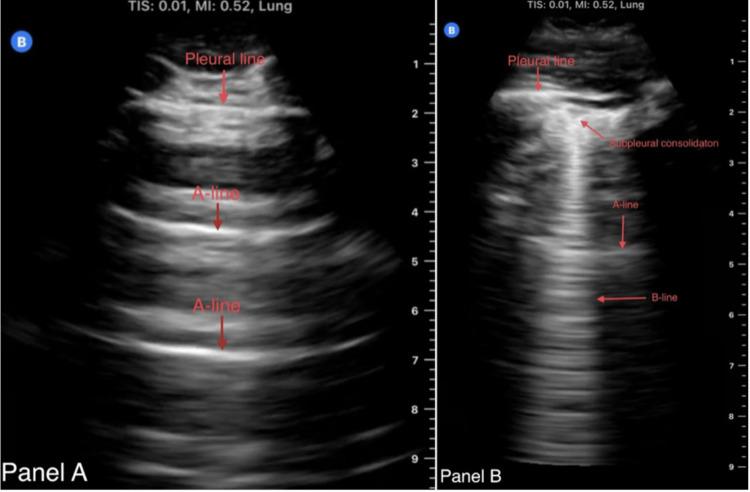

We report a case of a 41-year-old male diagnosed with pulmonary coccidioidomycosis and pulmonary embolism (PE) based on a point-of-care ultrasound (POCUS) finding who was suspected to be malingering for right-sided chest pain considering his psychiatric history. POCUS was performed and showed right ventricular strain with a D-shaped left ventricle and B-lines with subpleural consolidations, and PE was confirmed with computed tomography pulmonary angiography. No other risk factors for PE were found except for coccidioidomycosis. The patient was treated with apixaban and fluconazole and discharged in stable condition. We discuss the usefulness of POCUS in diagnosing PE and the very rare association between coccidioidomycosis and PE.

我们报告了一例41岁男性病例,该患者基于床旁超声(POCUS)检查结果被诊断为肺球孢子菌病和肺栓塞(PE)。考虑到他的精神病史,曾怀疑他右侧胸痛是装病。进行了POCUS检查,结果显示右心室劳损,左心室呈D形,并有胸膜下实变的B线征,随后通过计算机断层扫描肺血管造影证实了肺栓塞。除球孢子菌病外,未发现其他肺栓塞危险因素。该患者接受了阿哌沙班和氟康唑治疗,出院时病情稳定。我们讨论了POCUS在诊断PE中的作用以及球孢子菌病与PE之间极为罕见的关联。